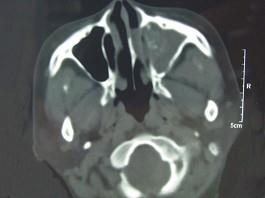

男,41岁,左侧鼻腔胀痛半年余,CT检查如图,最可能诊断为 ( )

• A.真菌性鼻窦炎

• B.出血坏死性息肉

• C.变应性鼻窦炎

• D.化脓性鼻窦炎

• E.上颌窦癌

答案: A